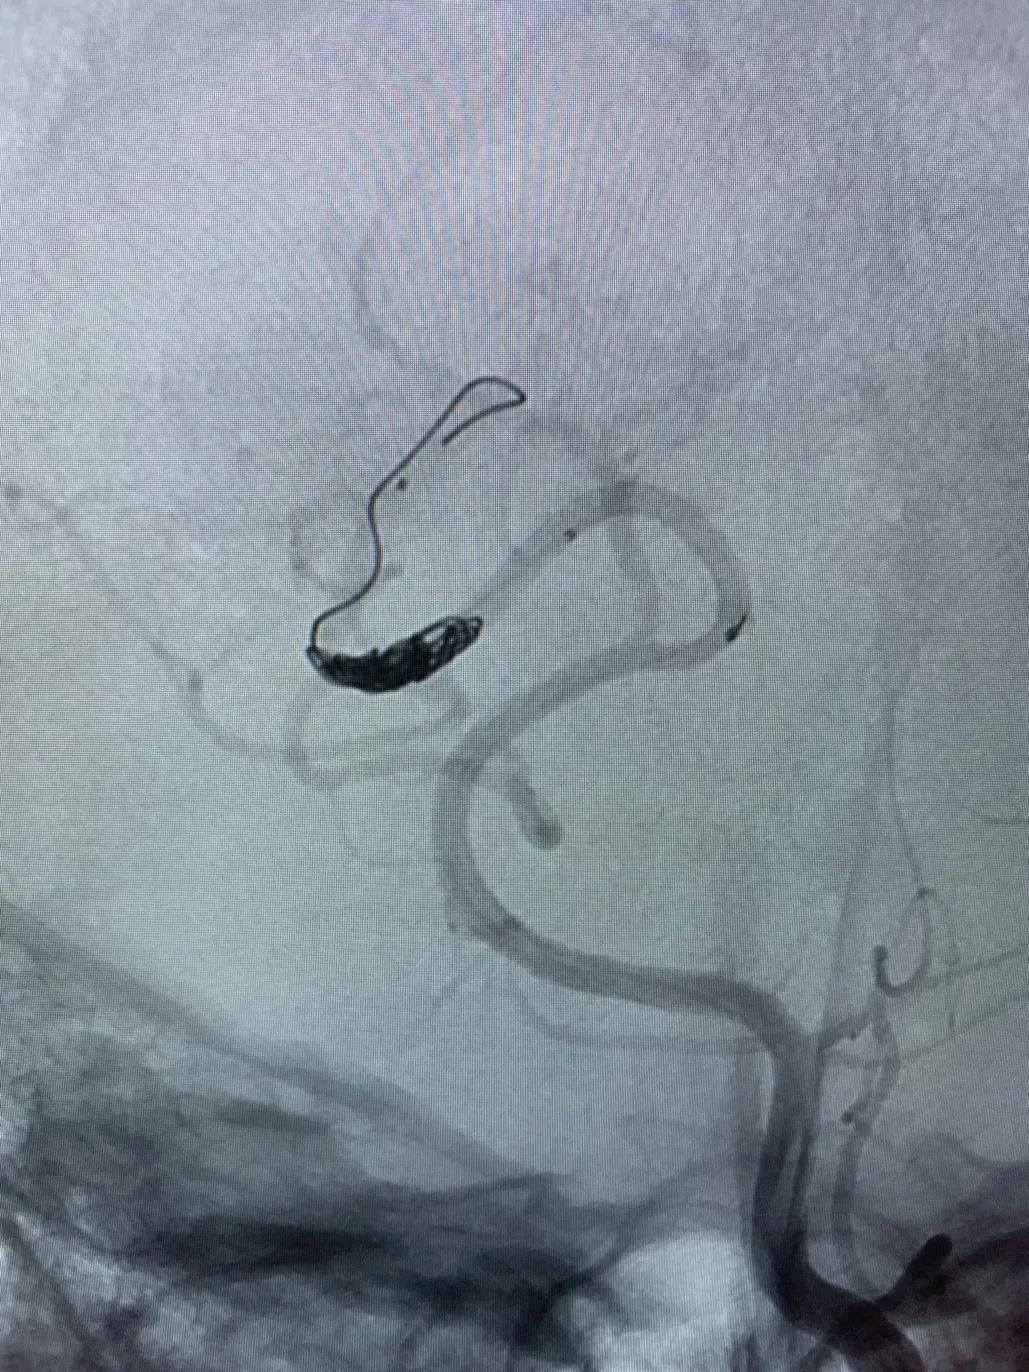

高压锅技术(Pressure Cooker Technique,PCT)是指在使用可解脱微导管进行Onyx栓塞时,在其可解脱点和导管远端之间,用另一根微导管(较细血管使用Magic,较粗血管使用10系列微导管)注射弹簧圈或nBCA等形成塞子,阻止Onyx返流,实现更好的栓塞效果。